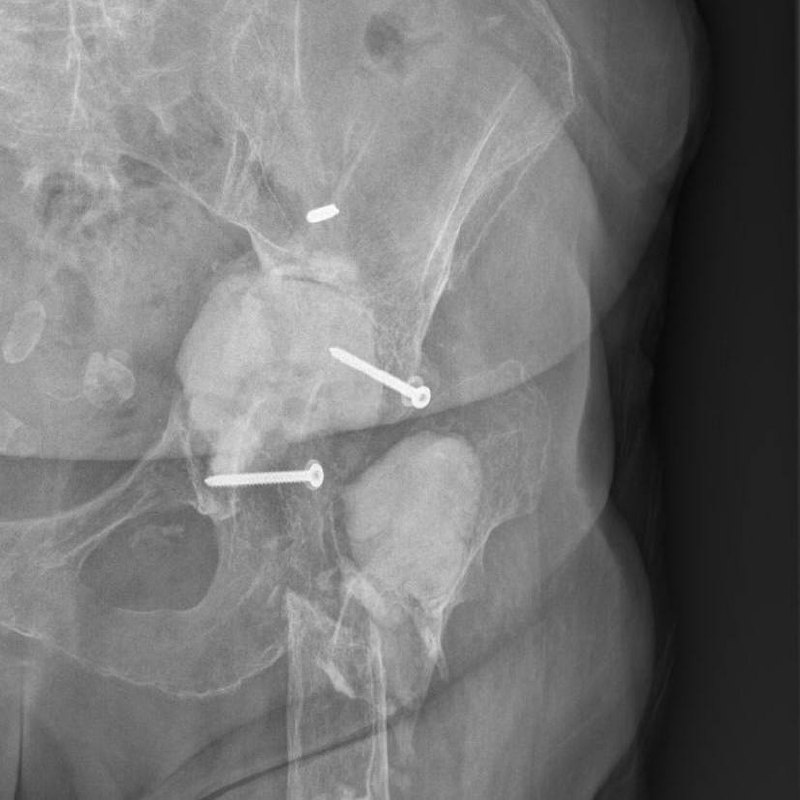

В НМИЦ фтизиопульмонологии и инфекционных заболеваний Минздрава России хирурги провели уникальную операцию пациентке, которая несколько лет страдала от тяжёлых последствий травмы таза и перипротезной инфекции.

После ДТП и нескольких операций у женщины сформировались обширные дефекты костей, из-за которых стандартные импланты уже не подходили. Риск повторной инфекции и потери функции сустава был крайне высок.

👨‍⚕️ Команда травматологов под руководством д.м.н. Ярослава Рукина приняла решение использовать индивидуальный титановый имплант, созданный на 3D-принтере по данным КТ. Конструкция идеально соответствовала анатомии пациентки, а заранее рассчитанные отверстия позволили точно установить фиксирующие винты, обеспечив стабильность.